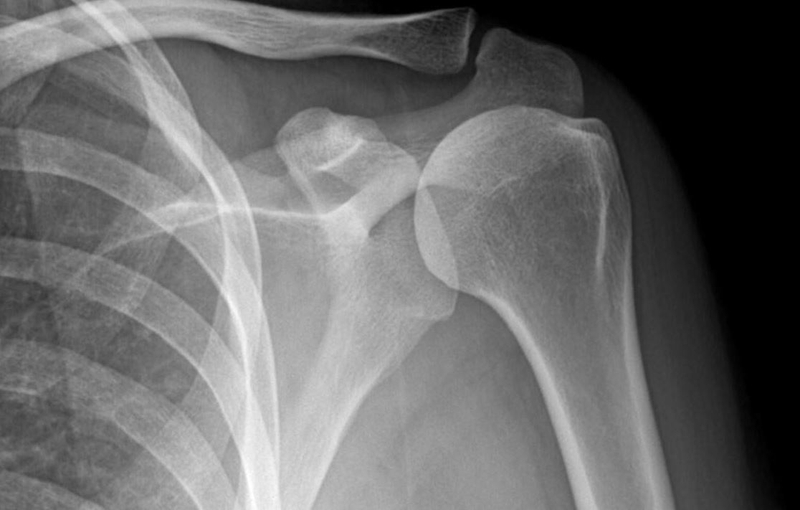

Chụp X-quang là kỹ thuật tầm soát bằng hình ảnh phổ biến nhất hiện nay. X-quang cho kết quả nhanh chóng chỉ sau vài phút với hình ảnh chụp rõ nét về hệ xương khớp, ổ bụng, khoang ngực và rất nhiều cơ quan khác trong cơ thể. Nhờ hình ảnh chụp X-quang các bác sĩ sẽ chẩn đoán chính xác và đưa ra phác đồ điều trị phù hợp nhất. Kỹ thuật chụp X-quang thường được chỉ định trong thăm khám và điều trị các bệnh lý về xương khớp, tim mạch, hô hấp,…